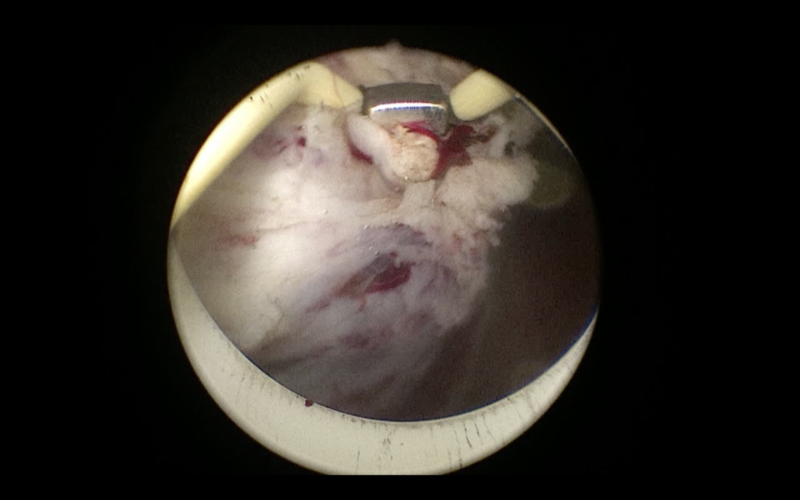

- το αδένωμα τεμαχίζεται και αφαιρείται με τη βοήθεια του morcellator το οποίο εισάγεται μέσα από τον αυλό του ενδοσκοπίου (εικόνες 7-9)

- οι λεπίδες του morcellator τεμαχίζουν το προστατικό αδένωμα και τα κομμάτια αφαιρούνται με τη βοήθεια αντλίας με αρνητική πίεση

εικόνες 7-9